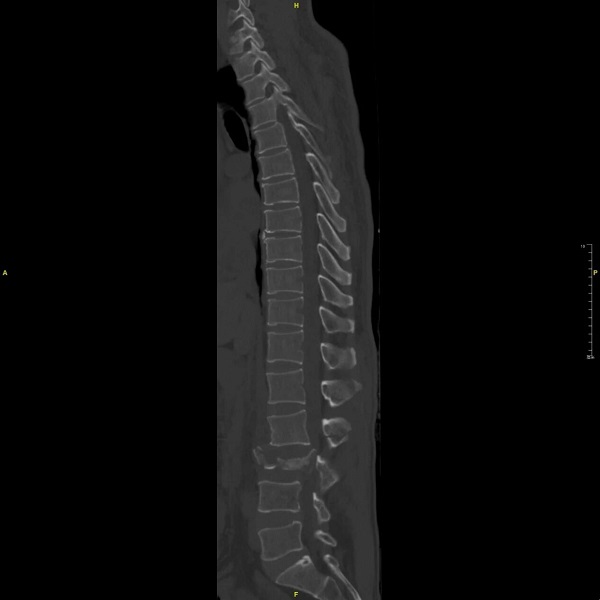

影像检查证实了最坏的预想:第三节腰椎如被炸裂般粉碎(爆裂型骨折),一块巨大的骨折片向后翻转,占据了超过95%的椎管空间,将负责下肢运动、感觉与二便功能的关键神经束——“马尾神经”,死死卡压、严重扭曲。

术前图片:腰3椎体爆裂性骨折,椎管占位严重